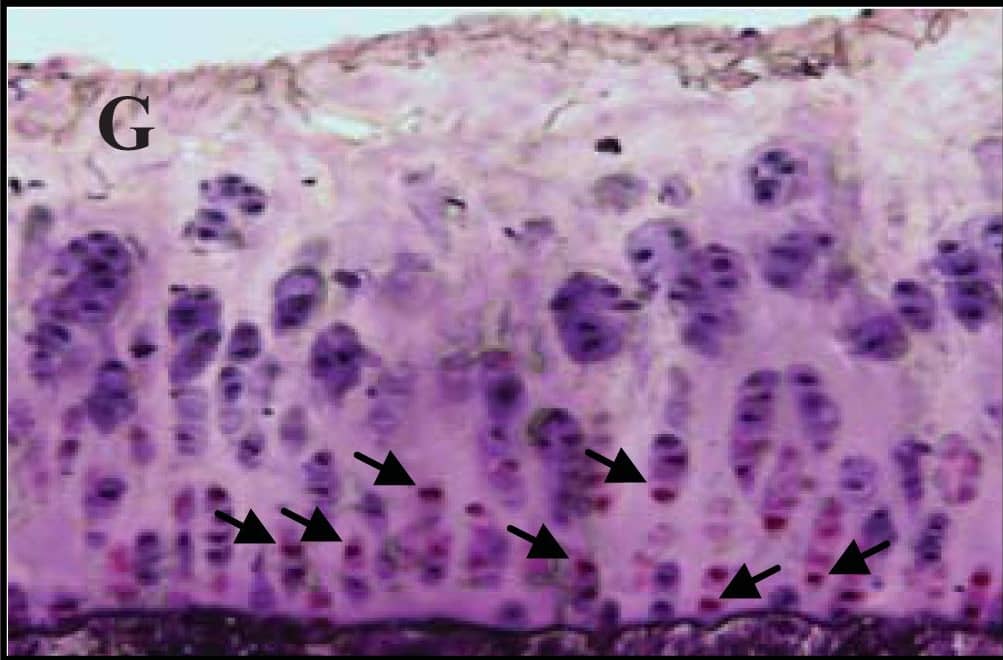

Detection of Guinea Pig Caspase-3 by Immunohistochemistry

Representative sections of the medial side of right tibial epiphysis stained with/without caspase-3. Sections stained with caspase-3 antibody at four different time points (DH: A, C, E and G; BS2: B, D, F and H); a higher magnification (I); the growth plate (J) and fibrocartilage of anterior cruciate ligament (K) show caspase-3 positive cells (red cytoplasmic staining; arrow). A negative control section is shown in (L). Image collected and cropped by CiteAb from the following publication (https://www.mdpi.com/1422-0067/14/9/17729), licensed under a CC-BY license. Not internally tested by R&D Systems.